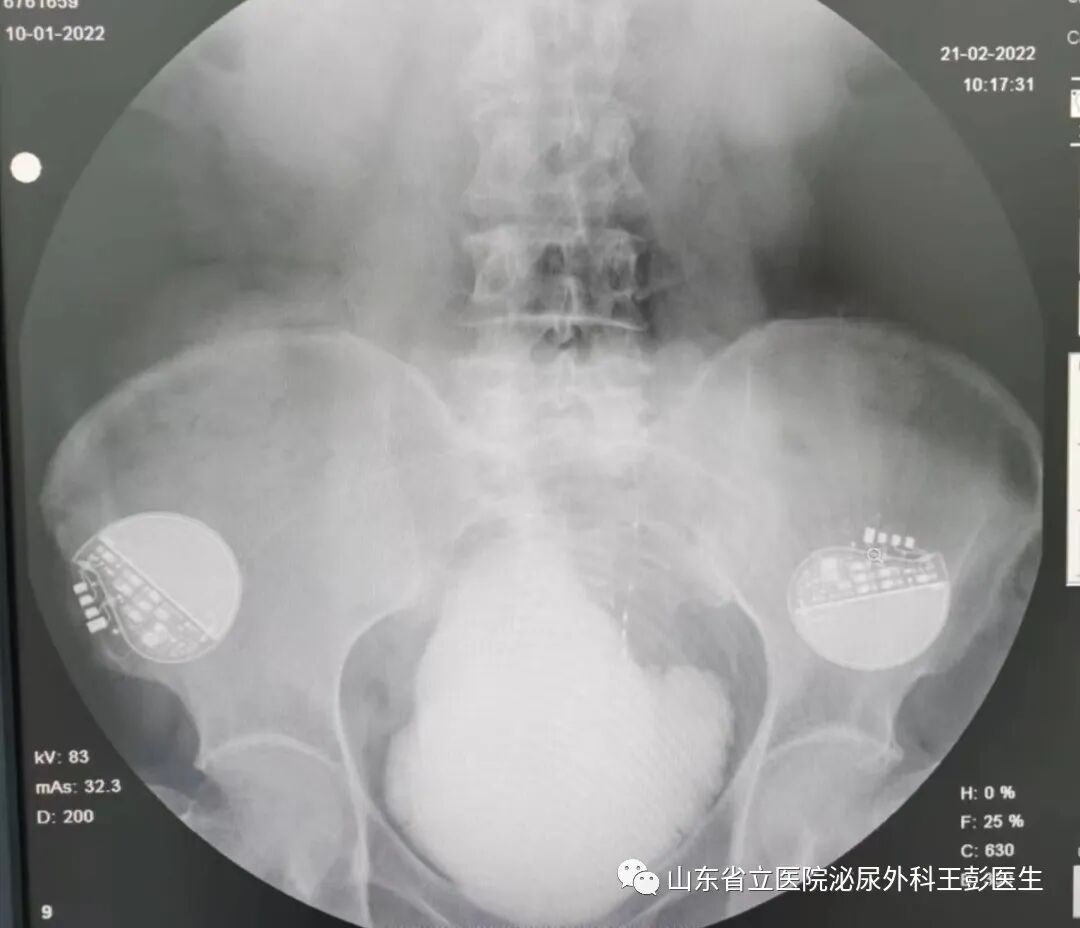

经过综合考量,我们决定为患者行双侧骶神经刺激器植入术术后患者膀胱容量恢复到约500ml,没有输尿管返流情况,同时尿频尿不尽的情况也得到极大缓解。

图片图片

术前VS术后